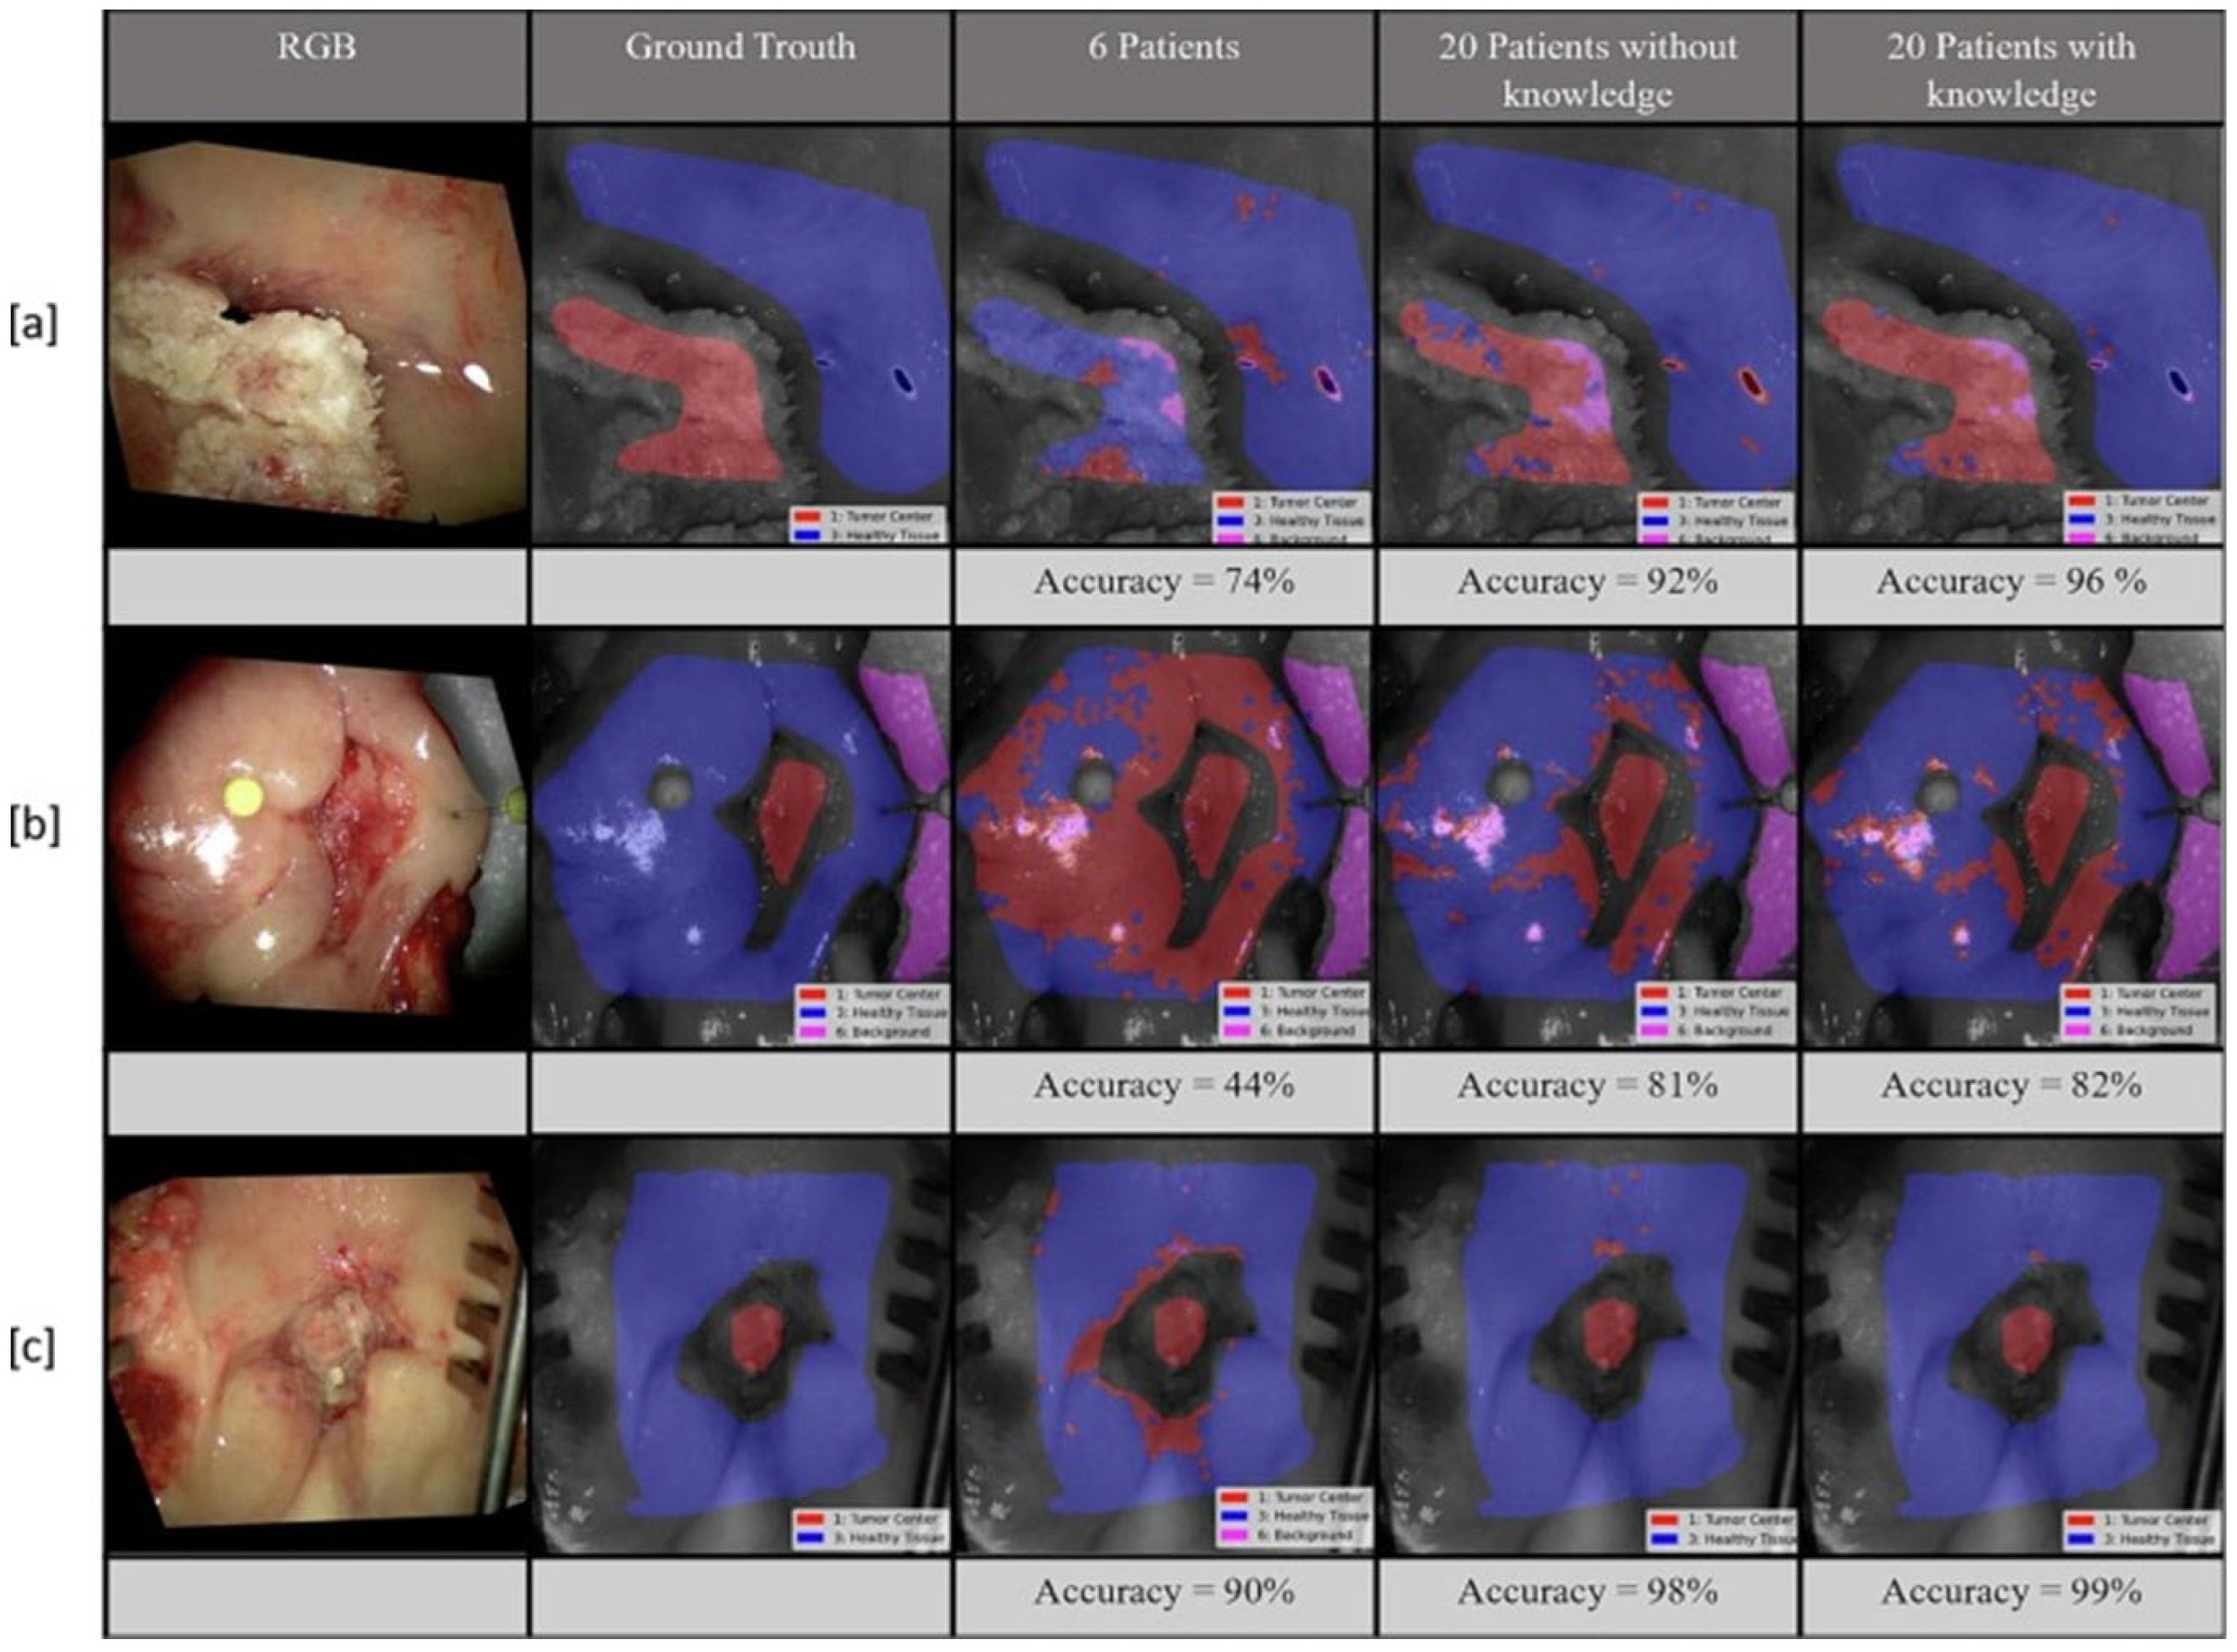

7.1. Detection of Tumors

- Römer, P.; Ponciano, J.-J.; Kloster, K.; Siegberg, F.; Plaß, B.; Vinayahalingam, S.; Al-Nawas, B.; Kämmerer, P.W.; Klauer, T.; Thiem, D. Enhancing Oral Health Diagnostics with Hyperspectral Imaging and Computer Vision: Clinical Dataset Study. JMIR Med. Inform. 2025, 13, e76148. [Google Scholar] [CrossRef]

- Giannantonio, T.; Alperovich, A.; Semeraro, P.; Atzori, M.; Zhang, X.; Hauger, C.; De Vleeschouwer, S. Intra-Operative Brain Tumor Detection with Deep Learning-Optimized Hyperspectral Imaging. In Optical Biopsy XXI: Toward Real-Time Spectroscopic Imaging and Diagnosis; SPIE: Bellingham, WA, USA, 2023; Volume 12373, pp. 80–98. [Google Scholar]